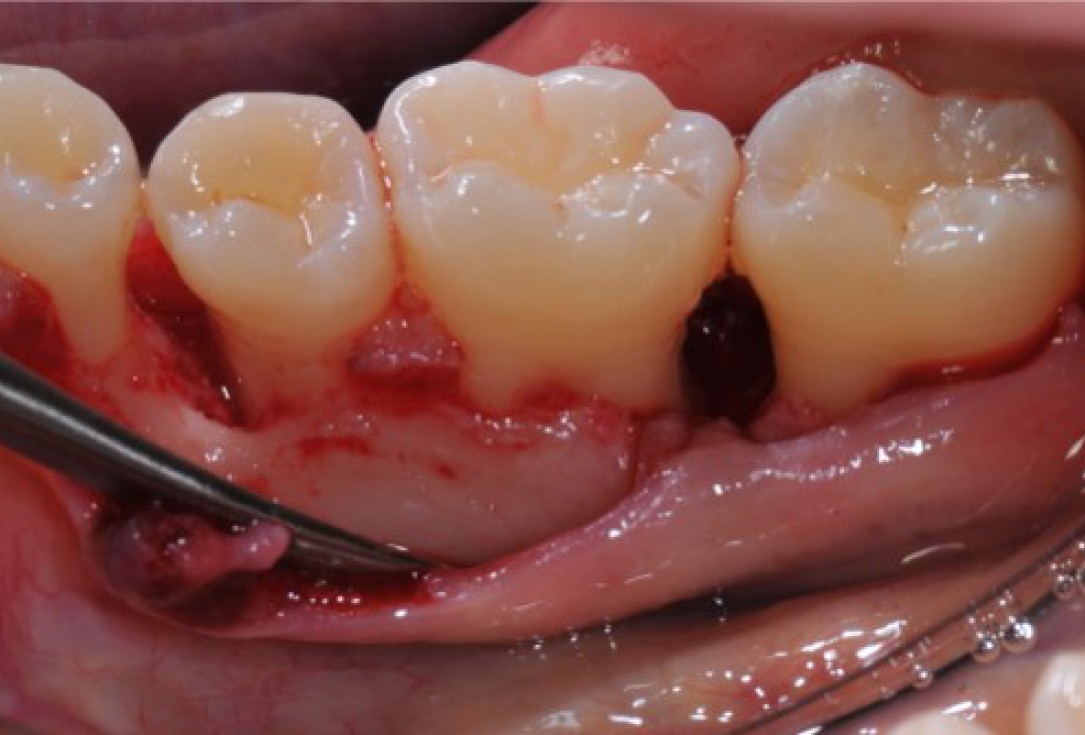

Initial situation: 40 year old female patient with extensive scar tissue after several surgeries restored with a Rochette bridge